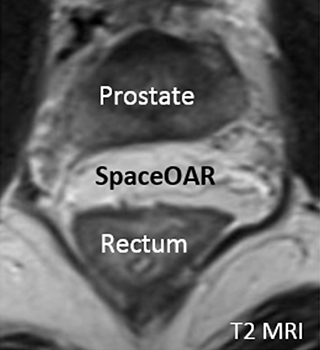

SpaceOAR®システムのMRI画像

体軸断面

放射線の影響は距離が離れれば低減します。そのため、当院では前立腺と直腸の間にゲル状の物質を挿入し、前立腺と直腸の間を1.0~1.5cm離すことで直腸被曝を低減させる処置として、『直腸周囲ハイドロゲルスペーサ・SpaceOAR®』の留置を行っています。

ハイドロゲルは注入後、前立腺と直腸の間に約3カ月間スペースを維持し、その後約6カ月かけて体内に吸収されます。